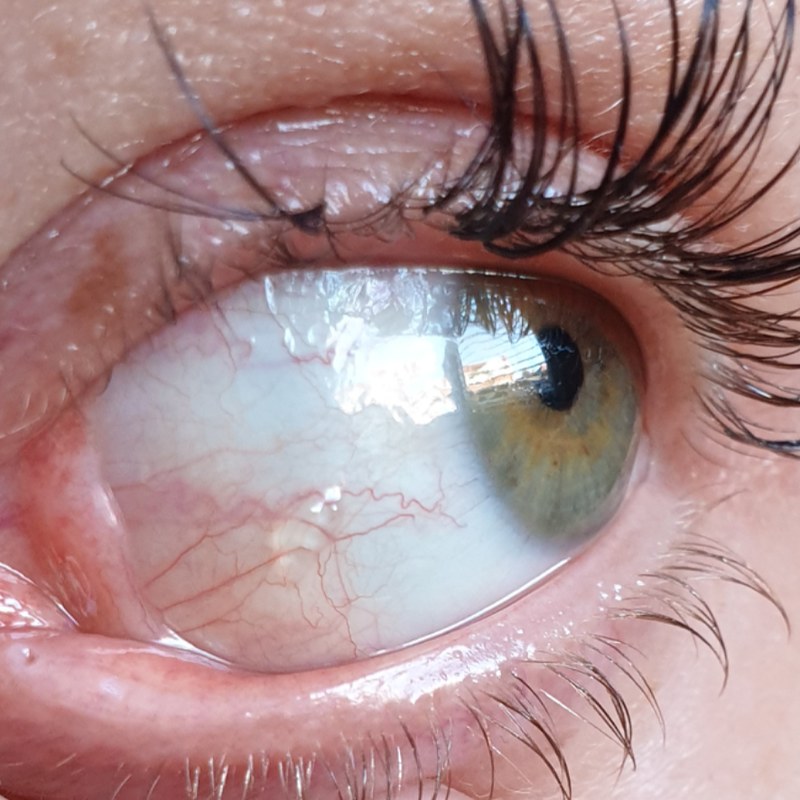

Bubble on eye – Page 1 – Health Matters – PistonHeads UK

Case of epiretinal membrane (ERM) in an eye with an axial length of …

Epiretinal membrane – Edgbaston Eye Clinic

Epiretinal Membrane – Retina Image Bank